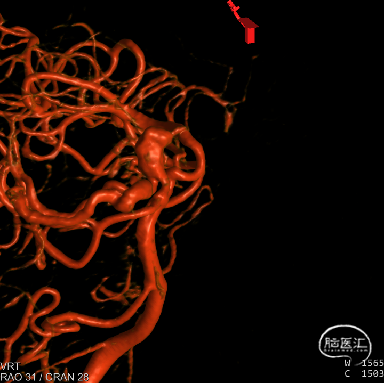

DSA:右侧P1段一6.8*9.7mm不规则囊状突起动脉瘤,远端P2段呈螺旋状蛇形动脉瘤改变。

DSA:右侧P1段一6.8*9.7mm不规则囊状突起动脉瘤,右侧A1段动脉瘤。夹层蛇形动脉瘤。

DSA:评估右侧后交通。

右侧颈内正位

右侧颈内3D

椎动脉压颈3D

动脉瘤参数:

动脉瘤大小为6.8*9.7mm,瘤颈宽4mm

载瘤动脉(颈内动脉)近端狭窄处为1.7mm,近端末狭窄处为1.4mm,远端为2.4mm。